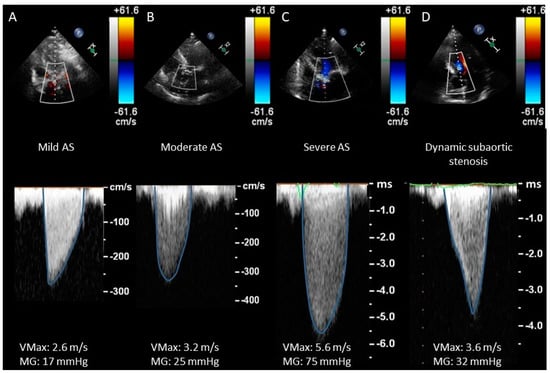

- CWD waveform (see Figure 4) is a semiquantitative parameter to evaluate the severity of AS. The finding of a CW waveform with a rapid acceleration and an early peak makes severe AS very unlikely. On the other hand, a slower acceleration with a late peak is more specific to severe AS. A dagger-shaped pattern may correspond to a dynamic subvalvular aortic stenosis (a common feature of obstructive hypertrophic cardiomyopathy) [27].

- Assessment of transvalvular flow velocity by Doppler technique is angle-dependent (see Figure 3).

- VMax and MG are flow-dependent parameters: high-flow states (i.e., fever, anemia, significant aortic or mitral regurgitation) or low-flow states (i.e., left ventricular systolic dysfunction or significant mitral stenosis) may, therefore, cause inaccuracy in AS grading.